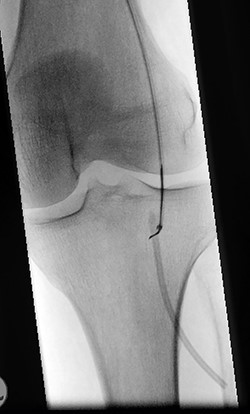

A 61-year-old male patient was diagnosed with inoperable stomach cancer. A TIVAD of the type Braun Celsite ST301® was inserted in the right subclavian vein for administration of chemotherapy. Location was confirmed by chest X-ray and the TIVAD was reported functioning with good backflow (Fig. 1). During initiation of the chemotherapy treatment, the TIVAD was reported malfunctioning. Contrast X-ray showed fibrin sheaths at the distal end of the catheter. An endovascular procedure was performed by an interventional radiologist and fibrin sheaths were mechanically removed with a snare (Fig. 2). Intraoperative X-ray with contrast showed normal contrast accumulation distal to the catheter tip and the patient received the first dose of chemotherapy. One month later the patient was hospitalized with bilateral pulmonary thromboembolism. The patient was treated with low-molecular-weight-heparin and discharged. The chemotherapy treatment continued as scheduled, with one pause due to a fracture of the right humerus after a fall. Occasionally, the TIVAD was malfunctioning and medication was administered using a peripheral venous catheter. During a planned pause in treatment, the patient sought hospital care due to worsening of his general condition. CT showed progress of malignancy and another round of chemotherapy was initiated and administrated using the TIVAD without any problems. Less than a week after, the patient reported feeling a tender swelling underneath his left foot. Ultrasound showed no DVT. The swelling and tenderness disappeared spontaneously, but the patient reported brief incidents of pain under his left foot. A CT scan was performed the next time the TIVAD did not function, showing that the distal 8 cm of the catheter was missing. The patient had no symptoms and reported no discomfort of any kind. The TIVAD was removed, confirming a fracture. A chest CT showed no foreign bodies. A full-body CT scan without contrast was performed, revealing the missing catheter part located at the level of the left knee (Figs 3 and 4). Vascular surgeons performed an endovascular procedure through the femoral vein assuming the catheter had embolized to the popliteal vein. Contrast examination revealed no catheter in the vein and another approach through the femoral artery was made, where contrast imaging shows that the catheter was, in fact, located in the popliteal artery (Fig. 5). The catheter, measuring 7.5 cm, was successfully removed with the use of a snare without any complications. The patient was discharged from hospital and referred to a diagnostic echocardiogram (Fig. 6). A bubble echocardiogram was performed to detect an atrial septal defect but was unsuccessful in doing so. For a final diagnosis, the patient was recommended a transesophageal echocardiogram, but as the diagnosis would not alter the course of treatment, the patient declined further examinations. Except for the reported episodes of pain and swelling of the left foot, the patient suffered no injury and finished his chemotherapy treatment.

Perioperative fluoroscopy during removal of fibrin sheaths with a snare.